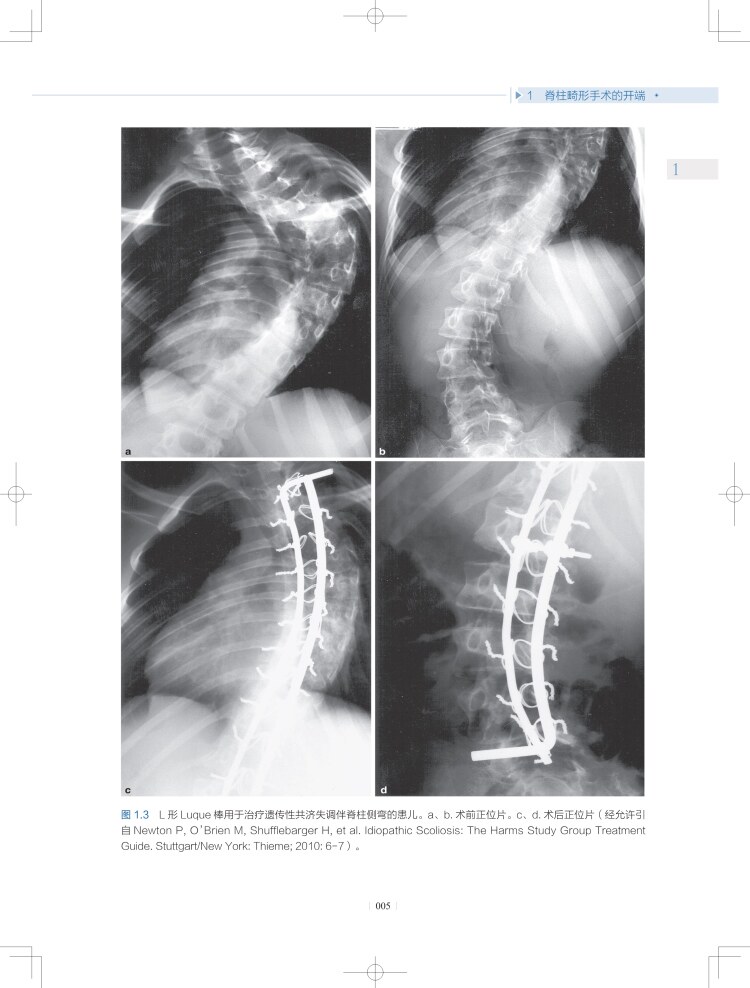

1 脊柱畸形手术的开端